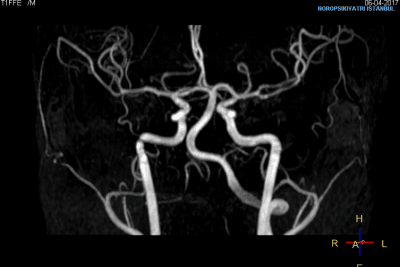

Beyin hastalıklarının tanı, tedavi ve takibinde gelişmiş görüntüleme teknolojilerinin kullanımı büyük önem taşımaktadır. Bu teknolojinin etkin kullanımı, hekimlere ayırıcı tanı koyma ve tedavi sürecindeki gelişmeleri takip etme imkanı sağlayarak hastalara büyük fayda sağlamaktadır. Kurum, beyin hastalıklarında en ileri görüntüleme cihazlarını kullanmakta olup, Türkiye'de ileri beyin MR tekniklerini ilk uygulayan kurumlar arasındadır.